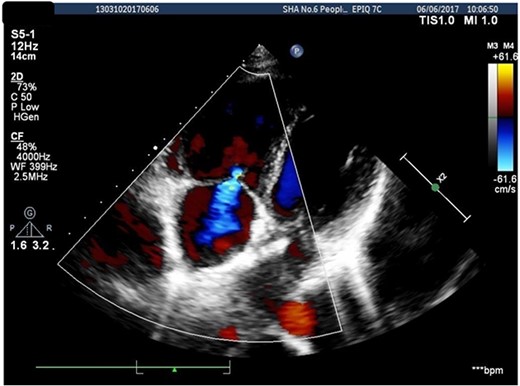

A 26-years-old woman comes to the hospital because of a 1-week history of fatigue. She has no history of serious illness and cardiovascular examination history. She can do light to moderate physical activity without developing dyspnea. Vital signs are within normal limits. Cardiac auscultation shows a heart murmur at the second intercostal space on the left sternal border and a wide-split S2 that does not change with respiration. Physical examination shows no bluish-colored lips or digital clubbing. The transthoracic echocardiography indicated atrial septal defect (Type II, diameter 25 mm); left-to-right bidirectional shunt, severe pulmonary hypertension (estimate PAP: 114 mmHg); right atrium and ventricular dilatation with severe tricuspid regurgitation (Fig. 1). Blood gas analysis showed: PH: 7.36, PaO2: 77.2 mmHg and PaCO2: 36.1 mmHg. The electrocardiogram was normal. Chest radiograph demonstrated pulmonary artery segment bulging suggesting severe PH. Right-heart catheter verified severe PH (PAP: 112 mmHg). Therefore, repair or closure of the ASD would be a high risk of developing a probable surge of pulmonary artery pressure. After serious consideration, we decided to treat her with a manual fenestrated closure device. Under general anesthesia and transesophageal echocardiography (TEE) guidance, the patient has inserted a handmade fenestrated Amplatzer Septal Occluder (reserved hole 5 mm, Abbott, St. Paul, MN, USA; Fig 2) through the right femoral vein, occlusion of the occluder in advance. After the device was released, TEE showed a slight left-to-right shunt. After the procedure, the patient’s oxygen saturation was 100%. On the second day after surgery, this patient was discharged. Echocardiography was performed in the second month and sixth month since discharge, and the PAP was 68 and 34 mmHg, respectively. Meanwhile, tricuspid regurgitation was reduced to mild. The right atrium and right ventricle size also decreased compared with preoperative. Therefore, the patient’s PH was reversible since the PAP decreased significantly after the first-step procedure. Thus, after careful evaluation, we take the second stage of the procedure to re-plug the 5-mm reserved hole by using the Amplatzer Septal Occluder (Abbott, St. Paul, MN) to eliminate the shunt Fig. 3). The surgery was successful and the patient was discharged the next day.

Transthoracic echocardiography suggested secondary atrial septal defect.